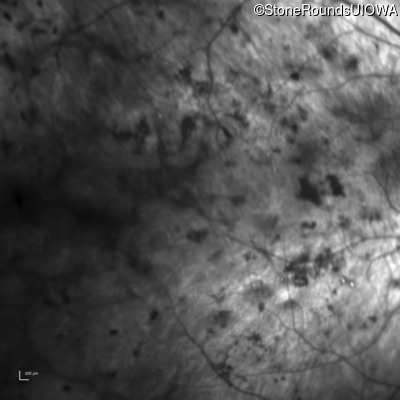

Age at visit: 61 years